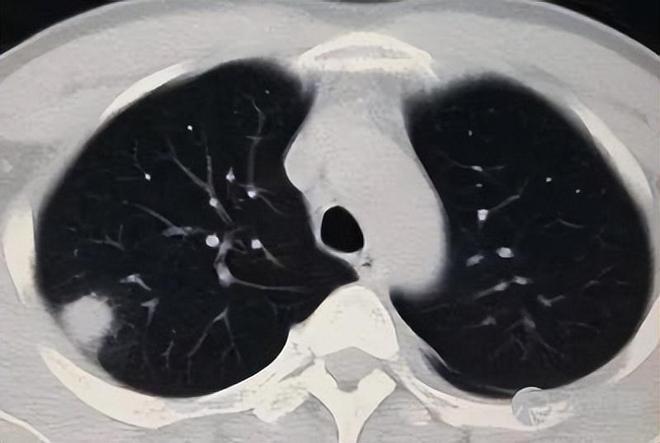

除了肥胖或超重、脂肪肝以外,肺部健康不容忽视,肺结节检出率已高达59.3%。肺结节指的是肺内直径小于或等于3cm的非正常组织,可以是圆形的也可以是不规则形状的。

由于出现肺结节大多没有症状,即便是查出肺结节,也多是良性的。一般也不用特定的治疗,通常每半年到一年复查一次即可。在日常生活中,需要注意戒烟戒酒、戒槟榔,保持良好的饮食和睡眠习惯以及积极向上的心理情绪即可。